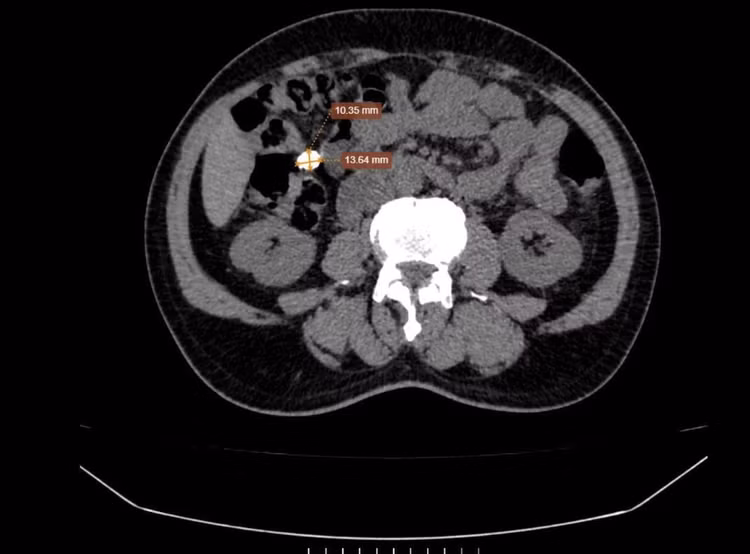

Để mang lại kết quả chính xác nhất, chuyên gia đã chỉ định bệnh nhân T. thực hiện chụp cắt lớp vi tính (CT) ổ bụng. Hệ thống CT 128 dãy hiện đại với khả năng tái tạo hình ảnh siêu sắc nét đã đưa ra kết quả hoàn toàn bất ngờ - không phải sỏi thận như chẩn đoán suốt nhiều năm qua mà là nốt vôi hóa thành ổ bụng (Kích thước ~ 15x10mm).

Hình ảnh trên phim chụp CT 128 dãy ổ bụng - Ảnh BVCC